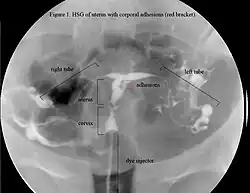

Sie hat damit die Hysterosalpingografie praktisch vollständig abgelöst, bei der sich Füllungsdefekte des Cavum uteri, der Tubenenden oder der Tubenostien, je nach Ausdehnung und Lokalisation der Adhäsionen darstellen ließen. Sie ermöglichte es jedoch nicht, eine klare Aussage zu treffen, was die Ursache für diese Füllungsdefekte ist.[4]